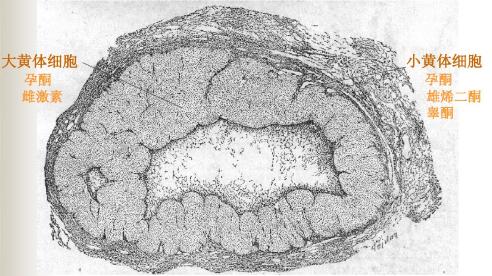

卵泡的发育是黄体形成的前提,排卵后卵泡颗粒细胞发生黄素化而变成黄体中“大黄体细胞”,卵泡膜细胞变成“小黄体细胞”,黄体细胞分泌孕激素。